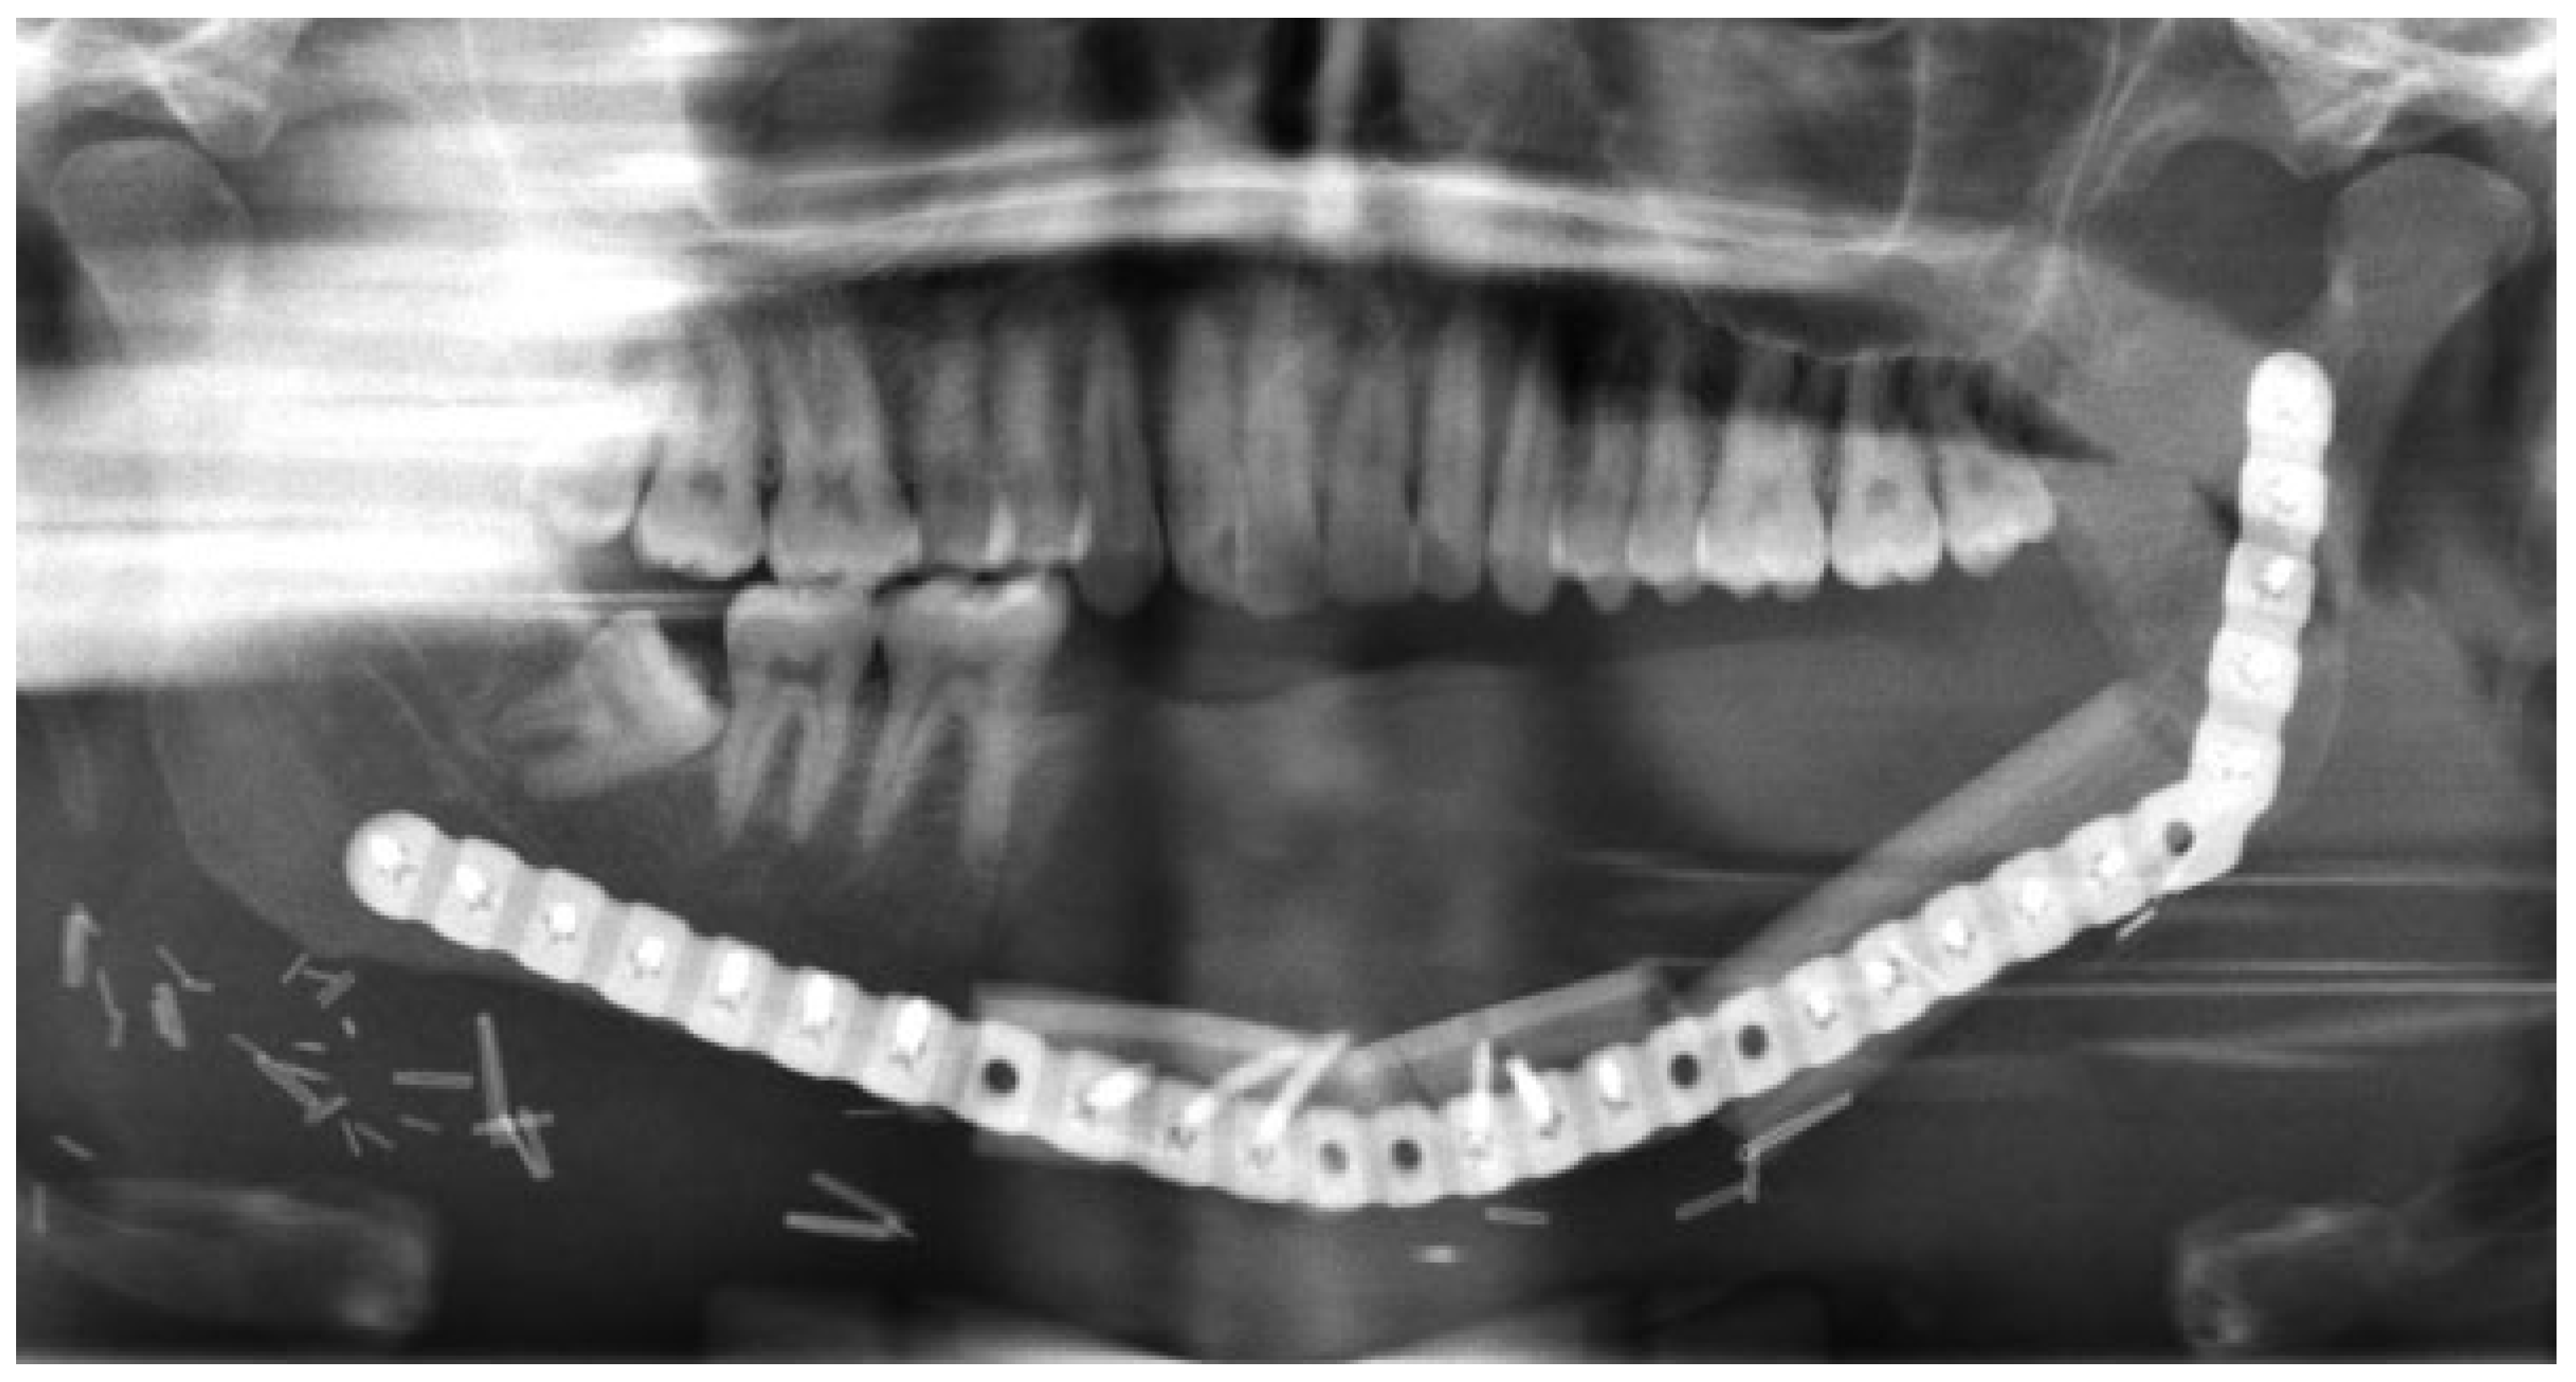

The third case was a 29-year-old white male with an expansile lesion of the anterior mandible. Panoramic radiograph showed a multilocular lesion involving the inferior border of the mandible and extending from the left second molar to the right canine (Figure 1). Incisional biopsy proved this lesion to be an ameloblastoma. The treatment plan included mandibular resection with 1-cm margin and immediate reconstruction with a free fibula microvascular flap. A tracheostomy for airway protection was also planned. A high-resolution CT scan was obtained followed by construction of a model. A custom prebent plate was obtained using the model as a reference. Using a combined transoral and transcutaneous approach, the mandible was resected from the left angle through the right second bicuspid. The 2.4-mm prebent reconstruction plate was placed (Figure 2). A free microvascular fibula flap with a skin pedicle was harvested. The fibula was contoured and adapted to the inner aspect of the custom-bent plate and secured with nonlocking screws (Figure 3). The skin pedicle was used to close the resulting soft tissue defect at the floor of the mouth. A tracheostomy was performed at the end of the case. The total surgical time including all the procedures was 10 hours and 33 minutes.

Figure 3. Postoperative panoramic radiograph. Reconstruction plate with free microvascular fibula graft in place, secured to the plate. Case 3.